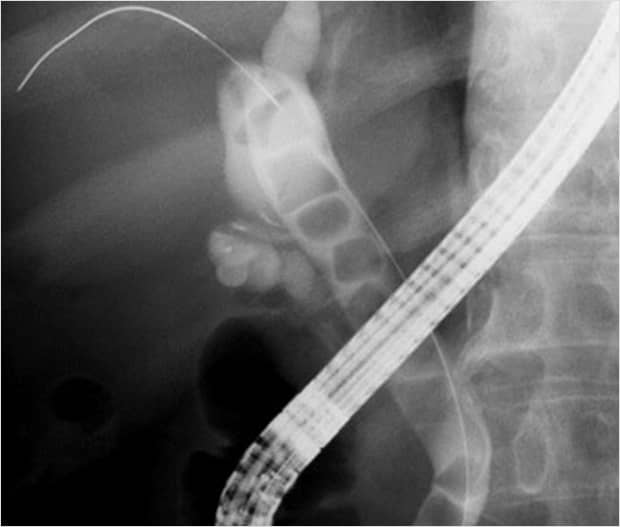

[ERCP画像]

内視鏡的逆行性胆管造影による胆管像、総胆管内に多数の結石を認めるも、開腹することなく内視鏡的に治療可能です.